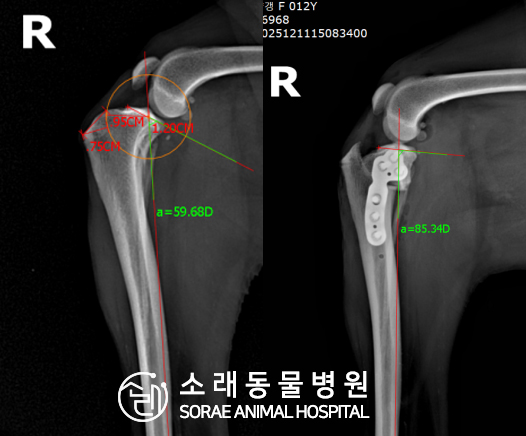

계산식으로 사전에 계획해두었던 플랜에 따라 경골을 절제하고

플레이트와 스크류를 사용하여 임플란트를 적용해 주었습니다.

반대 방향으로 밀려나 어긋나있던 대퇴골과 정강이가

제 자리를 찾으면서 무릎의 각도가 교정된 것을 확인할 수 있습니다